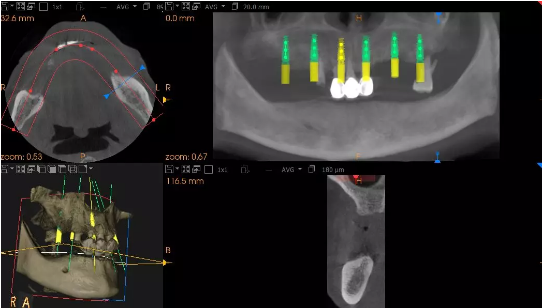

患者术前模拟方案

美莱口腔深圳店周炜院长经过了综合检查与评估,确认韦爷爷可以进行种植牙手术。确认韦爷爷无手术禁忌症,制定出“即刻种植”手术方案,该技术可以实现在一天内完成缺牙种植,微创无痛,当天种完当天用。经过1个多小时的手术,周炜院长顺利为韦爷爷完成了上颌的牙齿种植,下牙部分韦爷爷继续选用活动义齿修复,术中韦爷爷无任何不适。

患者术后口腔全景片-上颌种入6个种植体